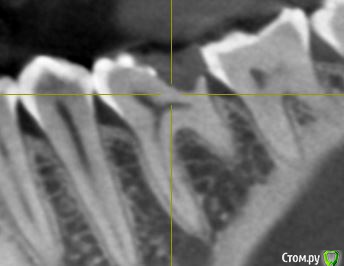

Сделала КЛКТ для того чтобы посмотреть насколько близко к пульпе располагается пломба. Однако материал данной реставрации оказался нерентгеноконтрастным. Так что только такой снимок зуба.

Также прилагаю снимок до лечения (там реставрация видна).

post-57670-0-09878900-1559650982_thumb.jpg